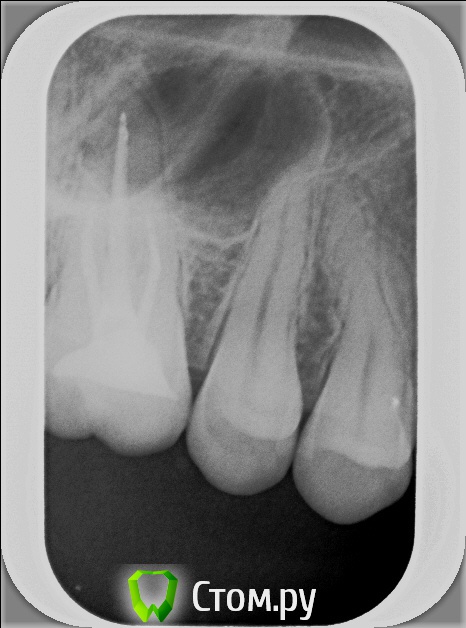

xSlon Опубликовано 13 августа, 2014 Поделиться Опубликовано 13 августа, 2014 Доброго времени суток!Прошу вашей помощи по сложному зубу, который не могут вылечить уже очень длительное время. Около 3х лет назад обнаружил, что при постукивании по 16му зубу(он был запломбирован совсем давно, не помню даже где и в каком году) появляется небольшая боль. Зуб не мешал, не доставлял беспокойств, но решив, что в таких случаях нужно действовать превентивно, пошел к стоматологу и рассказал о проблеме. Он посмотрел зуб(без вскрытия), сказал что никаких признаков боли не видит и считает что нужно удалять нерв. Поскольку зуб проблем не доставлял, я отказался.В течение этих трех лет состояние не ухудшалось, но я еще два раза ходил к разным стоматологам, описывал симптомы, они смотрели зуб, никаких признаков болезни не видели и советовали заниматься зубом когда он будет доставлять настоящие неудобства.В середине октября 2013 года ситуация ухудшилась, зуб начал периодически не сильно болеть, реагировать на холодное и горячее. В середине декабря ситуация сильно ухудшилась, зуб начал сильно болеть, сильно реагировать на холодное и горячее, сильно болеть даже при простом касании. Я обратился в стоматологию1 к врачу1, где мне вскрыли зуб, сказали что обнаружили под пломбой кариес, из-за кариеса произошло воспаление нервов и нужно удалять нервы в зубе. Боль была очень значительной, я не раздумывая согласился. Мне вскрыли зуб, поставили обезболивающее(или лекарство - точно не знаю), и сказали прийти через 7 дней, боль прошла. Через 7 дней мне обработали каналы и запломбировали Metapex'ом, сказали прийти в феврале(возможно еще удалили лекарство, точно не помню). В феврале мне за 1 посещение запломбировали постоянно каналы и за 2е посещение запломбировали зуб. К середине февраля лечение закончилось, жалоб не было. Единственное - удивляло что зуб, несмотря на удаление нервов, по старому реагирует на постукивание небольшой болью, но я не придал этому большого значения.Спустя 2 месяца, в середине апреля, остро заболел тот же самый зуб, с теми же симптомами - сильная боль, сильная реакция на холодное и горячее, сильная боль при касании. Врач1 был в отпуске, поэтому я пошел к Врачу2 в ту же самую Стоматологию1. Описал ситуацию, Врач2 посмотрела мою карточку, вскрыла зуб, осмотрела его, сказала что где-то должен быть 4й канал, но она не может его найти, сказала что вставила куда-то в зуб лекарство, сказала прийти через неделю.Боль утихла, пришел через неделю к тому же Врачу2, повторно вскрыли зуб, повторно поставили лекарство, но Врач2 сказала что 4го канала, который там должен быть, она не видит. Посоветовала обратиться к другому врачу, возможно, в другую стоматологию Через неделю, уже в начале мая, пришел повторно, запломбировали каналы Metapex'ом, поставили временную пломбу. По совету знакомых, в начале июня обратился к частному Врачу3, который специализируется на работе под микроскопом. Описал ей ситуацию, она вскрыла зуб, нашла четвертый канал, вставила туда лекарство, сказала прийти через неделю. Через неделю реакция зуба на слабые постукивания сохранилась, на приеме у Врача3 поставили более сильное лекарство(насколько я помню, с антибиотиком), прописала дополнительно в течении 5 дней пропить сильные антибиотики, сказала прийти через 10 дней. Через 10 дней, в конце июня, та же реакция зуба сохранилась. На приеме у Врача3 решили окончить лечение, потому как Врач3 на следующий день уходила в отпуск, а я, через несколько дней, уезжал в командировку. Перед отъездом пошел в Стоматологию1 к Врачу2, чтобы снять лекарство и временно запломбировать каналы и поставить временную пломбу. Врач2 сказала, что при вскрытии зуба она увидела 4й канал, попыталась определить длину канала с помощью прибора, используя самый тонкий инструмент(как я понял - это некая игла, подсоединенная к прибору, ее всовывают в канал, чем ближе кончик иглы к концу канала, тем сильнее он пищит), определить длину канала ей не удалось. Она предположила, что либо канал очень узкий, либо он изгибается, поэтому не удается дойти до конца канала.В командировке, в середине июля обновлял временную пломбу(от нее отвалился небольшой кусочек) в Стоматологии2, вкратце описал проблему Врачу4, он посоветовал использовать(дословно с листочка, который он мне дал) пломбировку материалом для к/к Forfenan Forident(резорцин-формалиновая паста). Сказал, что при таком методе, воспаленный нерв полностью обволакивается пастой, которая гермитизирует нерв, не давая разиваться воспалительному процессу. Сам воспаленный нерв остается, но организм, со временем, справляется с ним сам.Вернувшись из командировки, я пошел, по советам родственников, в Стоматологию3, к Врачу5. Описал ситуацию, сделал панорамный и прицельный снимки. Врач5, не вскрывая зуб, сказала что считает, что необходимо применить метод депофореза. Прошу вас, пожалуйста, посоветовать, каким образом вылечить этот зуб? Стоит ли попробовать резорцин-формалиновую пасту? Стоит ли делать метод депофореза? Возможно есть какие-то другие методы лечения? Прикладываю все снимки зуба из Стоматологии1Панорамный снимок из Стоматологии3, сделан 12 августа. https://yadi.sk/i/_hIqGP1IZaT4Y Ссылка на комментарий

xSlon Опубликовано 14 августа, 2014 Автор Поделиться Опубликовано 14 августа, 2014 Добавлен прицельный снимок 16го зуба от 12го августа. К сожалению, не нашел, как отредактировать первый пост. Ссылка на комментарий

Бобр Опубликовано 28 августа, 2014 Поделиться Опубликовано 28 августа, 2014 Интересно, возможно сначала идет один МБ, а потом он где нибудь в средней трети раздваивается? Возможно трещина. Возможно парадонтальный карман на медиальной поверхности. Честно говоря интересная история. Ссылка на комментарий

Scrabble Опубликовано 31 августа, 2014 Поделиться Опубликовано 31 августа, 2014 Я вижу, что Вам запломбировали каналы термафилами-причём два носителя введены в дистальный, а не в мезиальный щёчный корень. В качестве силера(пасты) использовался форфенан? Если это так, то нужно всё распломбировать, полностью удалить форфенан-и ждать, пока стихнет симптоматика. Ссылка на комментарий